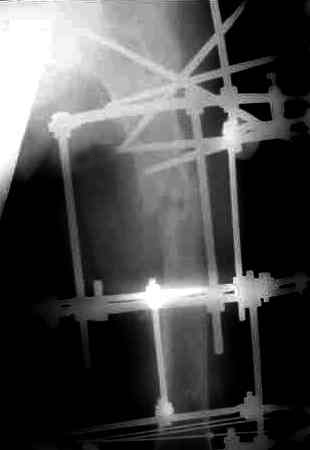

После нескольких некрэктомий, проведения аутодермопластики и заживдения ожоговой раны через 2 месяца после травмы произведен открытый остеосинтез левой бедренной кости штифтом и пластиной (деротационной) [image 01, 02]. Через 1 год и 7 месяцев после травмы у больного диагностированы ложный сустав и хронический остеомиелит левой бедренной кости. Произведено удаление металлических фиксаторов, секвестрэктомия и остеосинтез бедренной костивнешним двухплоскостным стержневым аппаратом [image 03, 04] .

Через 3 года после травмы констатировало отсутствие консолидации бедренной кости, сохранение признаков хронического остеомиелита (свищ в нижней трети левого бедра). Произведен демонтаж аппарата, реостеосинтез бедренной кости спице-стержневым аппаратом, некрсеквестрэктомия. В аппарате удалось лишь частично произвестиустранение углообразной деформации бедренной кости [image 05] .